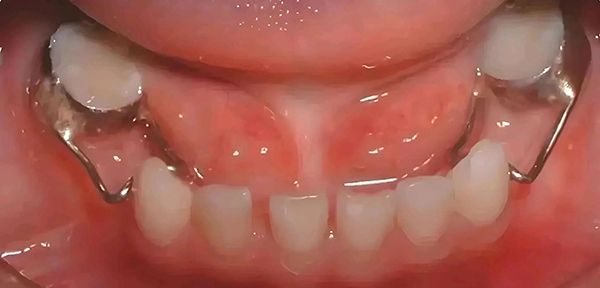

间隙保持器是一种用于儿童牙齿早失后,为保持空缺、维持正常生理间隙,防止邻牙向丧失部位倾斜和颌牙伸长而制作的装置。它能保持早失牙齿在牙列中的近远中和垂直间隙,确保继承恒牙正常萌出。

间隙保持器大体分为丝圈带环式、远中导板式、舌弓式、Nance 弓式、全冠式等。